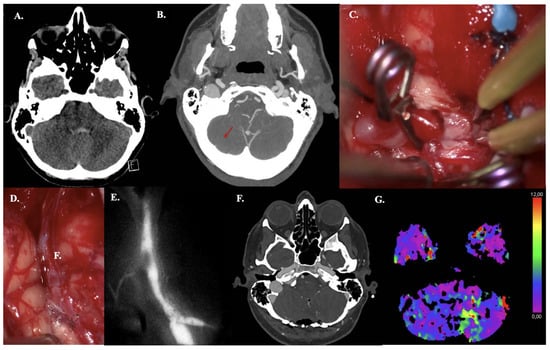

A 63-year-old man with a history of hypertension and atrial fibrillation presented with sudden loss of consciousness, left-side hemiparesis, and a spastic gait. MRA revealed a giant thrombosed MCA bifurcation aneurysm (size > 50 mm) accompanied by M1 occlusion and collateral formation (Figure 3A). CT perfusion revealed a right MCA territory perfusion deficit (with normal cerebral blood volume levels) (Figure 3B). DSA demonstrated no filling of the aneurysm from M1 but did demonstrate collateral filling from the Anterior Cerebral Artery and Posterior Cerebral Artery (Figure 3C). Microsurgical decompression of the aneurysm and revascularization to the hypoperfused areas were indicated due to the symptoms of mass effect and hemodynamic Transient Ischemic Attacks (TIAs). The latter was based on MCA territory hypoperfusion and insufficient collaterals from the posterior circulation, confirmed on preoperative CT perfusion (Figure 3B). Intraoperatively, the STA had a cut-flow of 60 mL·min−1. Before the anastomosis was performed, ICG videography showed a delayed time to drain of 11 s. After a STA-M3 bypass (Figure 3D–F) was performed, ICG videography confirmed bypass patency. The time to drain decreased to 7 s, and the STA had a measured flow of 30 mL·min−1. The aneurysm was then trapped proximally and distally. The thrombosed aneurysm sac was debulked to reduce mass effect. Postoperative CTA confirmed bypass patency. During hospitalization, he demonstrated transient mild hemiparesis and mild oculomotor palsy. Both were resolved within two months postoperatively.

Figure 3. Illustrative Case #14. 63-year-old male with giant (>50 mm), thrombosed MCA bifurcation aneurysm with M1 occlusion. (A) Time of Flight MRA sequence of giant thrombosed aneurysm. (B) CT perfusion (Cerebral blood flow) demonstrating right hemisphere MRA territory perfusion deficit. (C) DSA demonstrating M1 occlusion (red arrow) and collateral formation, no aneurysm sac filling. (D) STA-M3 anastomosis. (E) The M1 and aneurysmal neck with severe atheromatous plaque and calcifications. (F) A clip is used to trap the M1 segment, and embolectomy is performed inside the aneurysmal lumen with the CUSA. The wall of the aneurysm remains in situ.